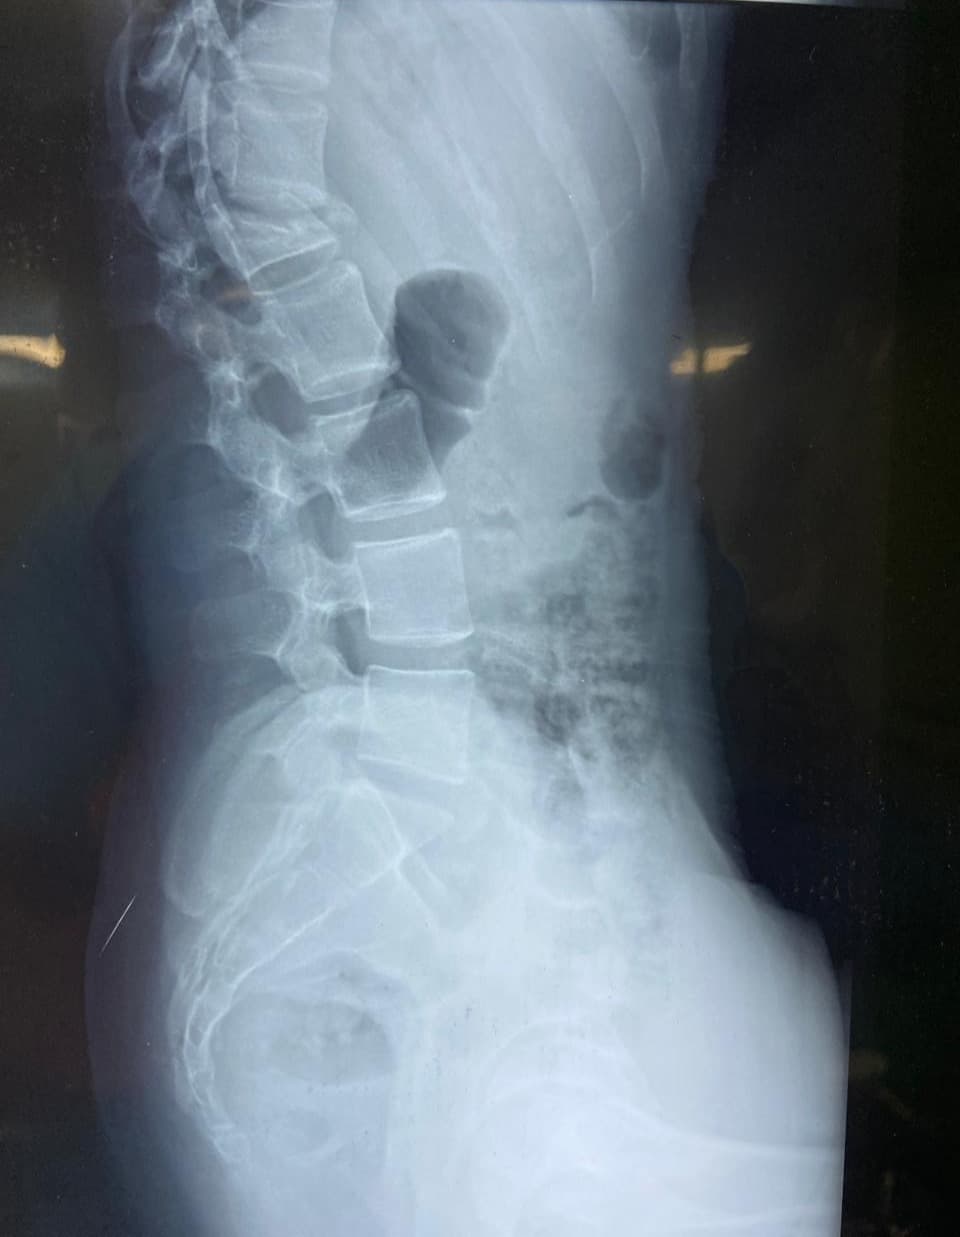

Spine fractures

A 17-year-old girl was brought to us after a fall from the first floor of her house. She had sustained a severe injury to her spine and was unable to walk at the time of admission. X-rays and MRI revealed an L1 burst fracture with compression over the spinal cord. On clinical examination, she had paraparesis—weakness of both lower limbs—with significant difficulty in standing and moving. The family was deeply worried as her ability to walk again was uncertain. Given the severity of the spinal cord compression and the risk of permanent neurological loss, she was taken up for emergency posterior stabilization and decompression of the spinal cord